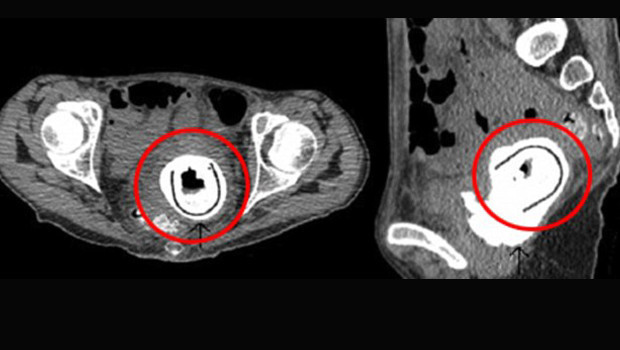

Herhangi bir zihinsel rahatsızlığı bulunmadığı gözlenen 38 yaşındaki kadının açıklaması ise “10 yıl önce partnerimle birlikte bu oyuncağı kullandım. O sırada alkolün etkisindeydim ve oyuncağı vajinamdan çıkarıp çıkarmadığımı hatırlamıyorum” şeklinde oldu.

Ameliyat sonrası “vezikovajinal fistül” (idrarın vajinaya sızması) ve “obstrüktif üropati” (idrarın böbreklere geri dönmesi) hastalıklarına yakalandığı anlaşılan kadın tedavi altına alındı.

Doktorlara göre sinir hücrelerinin bu kadar yoğun olarak bulunduğu vajina gibi bir bölgede yabancı bir cismin varlığını hissetmemek oldukça nadir görülen bir durum.